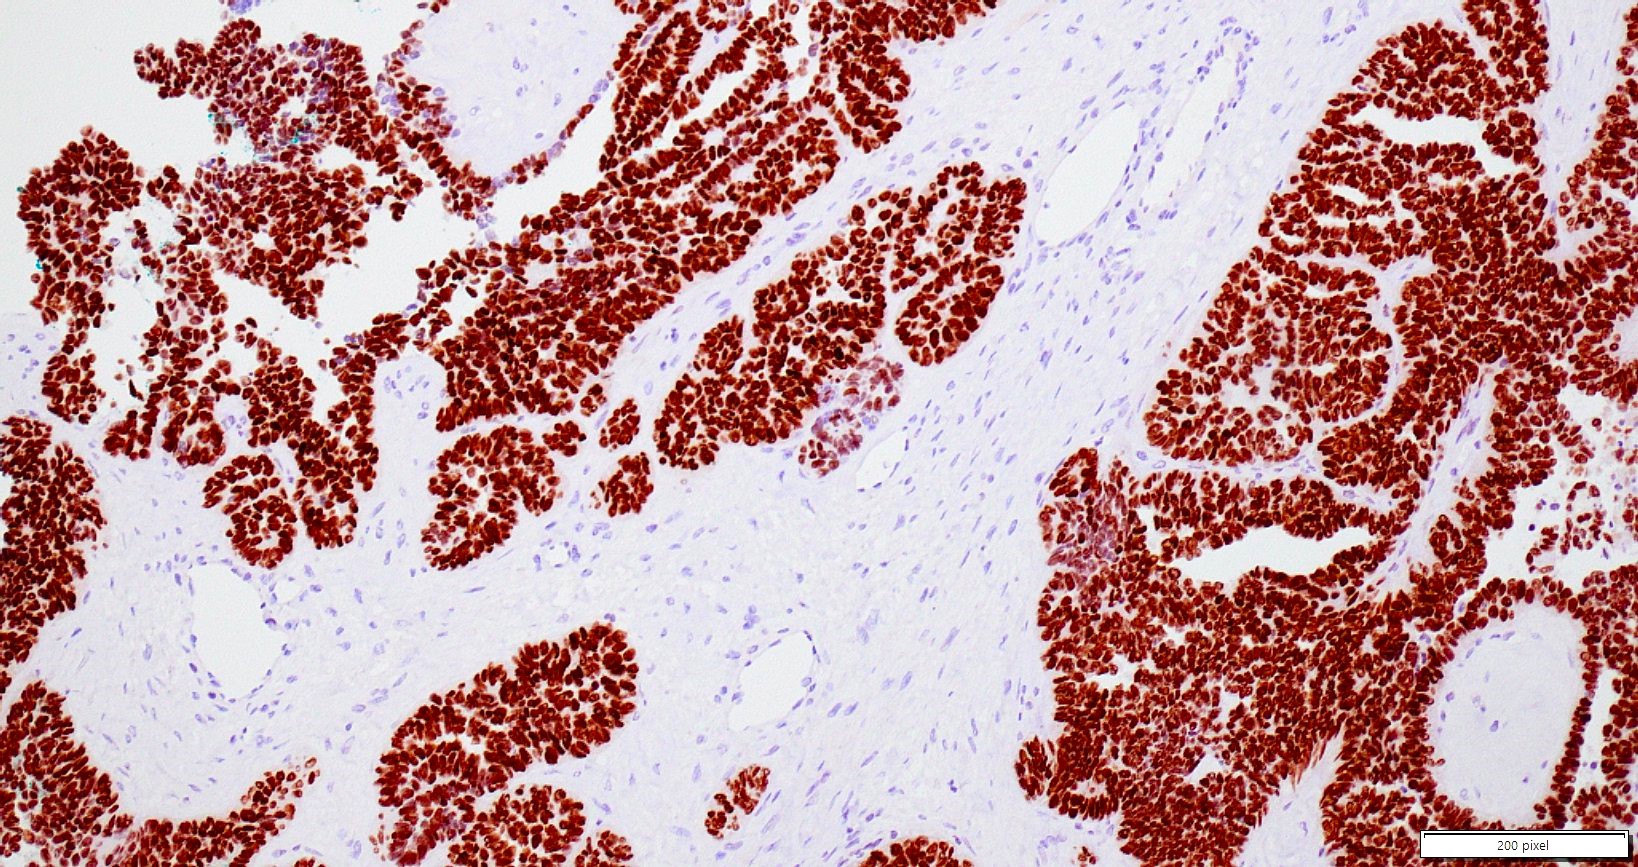

- Variety of histologic patterns that may be present within the same tumor

- Most frequently small tubules with ductal / glandular growth

- Papillary, solid growth, trabecular, retiform, sex cord-like, sieve-like, glomeruloid and spindle cell areas have all been described

- Luminal eosinophilic secretions are characteristic but not always identified

- Tumor cells can be flattened, cuboidal or columnar with mild to moderate cytological atypia

- Clear cell features can be seen but are less common

- High grade cytological atypia is usually not a predominant feature

- Nuclei show vesicular chromatin and nuclear grooves

- Sarcomatoid transformation has been seen in rare instances

- Squamous, ciliated or mucinous differentiation (metaplasia) are not present and there are no associated mesonephric remnants (J Clin Med 2021;10:698)

Microscopic (histologic) images

Contributed by Daniel Graham, M.D., Adele Wong, M.B., B.Ch., B.A.O. and Lucy Ma, M.D.